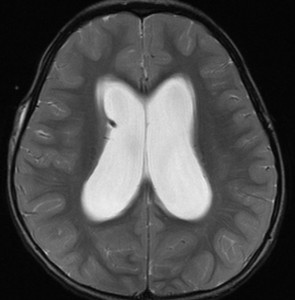

小脳虫部の毛様粘液性星細胞腫が第4脳室を閉塞して,閉塞性水頭症になっています。左の画像のように側脳室に水がたまってパンパンになっています。頭痛が生じて嘔吐しますが,ひどくなると意識障害となります。